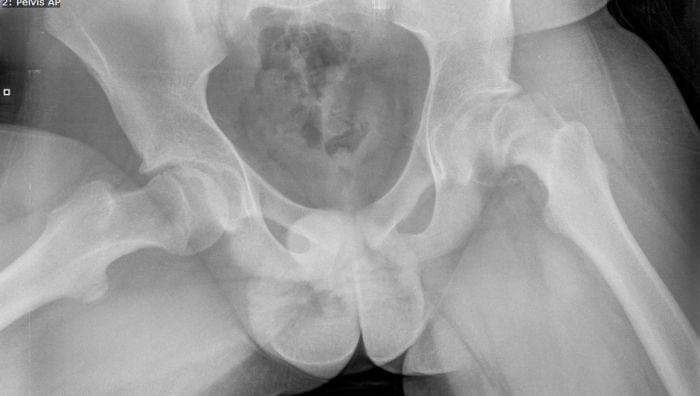

Operativni tim UKC Tuzla izveo rijedak operativni zahvat

Operativni tim Klinike za ortopediju i traumatologiju UKC Tuzla izveo je operativni zahvat proximalnog dijela...